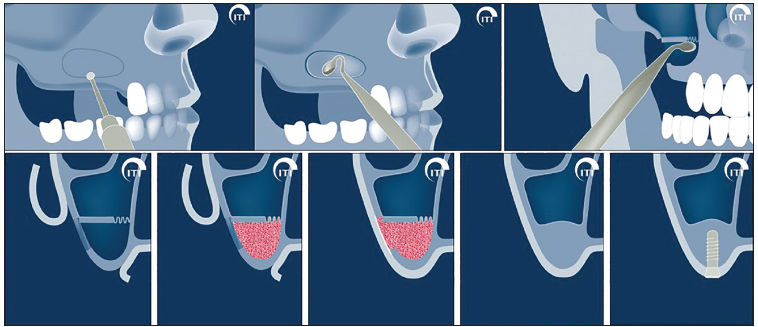

대략적인 도식은 이러합니다...

어금니가 없는 자리에 뼈이식을 많이 해야하는 상황이므로, (상악동 뼈이식술은 치과에서 뼈이식재가 가장 많이 사용되는 영역 중 하나입니다.) 측방접근법을 사용하게 됩니다.

가장 효율적이고 성공률이 높은 뼈이식 방법이며, 저희 한남동 치과에는 성공적인 상악동 뼈이식술을 위한 초음파 골삭제 기구 (PIEZO surgery)가 있어 상악동 막의 손상없이 훌륭한 임상결과를 내고 있답니다.

출처 : ITI

제가 애정하는 스위스 스트라우만 임플란트의 연구 기관인 ITI에서 따온 모식도를 보시면 이해에 보다 도움이 되실꺼에요... 여튼 높이로써 1mm의 뼈만 있으면 10mm의 임플란트도 심을 수 있게 해주는 수술이 바로 상악동뼈이식술입니다.

이 엄청난 술식 덕분에 많은 사람들이 틀니를 하지 않고 어금니 임플란트 치료를 받을 수 있게 되었죠...